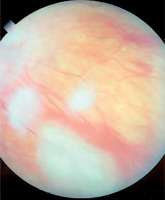

Symptoms of tuberous sclerosis (Bourneville disease, epiloia) involve multi-organ abnormalities of ectodermal and mesenchymal origin, causing abnormalities in the skin, brain tissues, central nervous system, kidneys, heart, lungs, and the organ of vision [14–16]. Skin changes may result from depigmentation, leading to lightening of the skin in areas affected by pigment loss. Facial skin redness may result from neurofibromas with a prominent vascular component. Additionally, raised patches resembling an orange peel texture (shagreen skin) are often observed, particularly on the dorsal region. Cerebral manifestations include autism spectrum disorders and epileptic seizures. Neurological complications are the leading cause of morbidity, whereas renal disease represents the primary cause of mortality. Another possible manifestation is lymphangioleiomyomatosis (LAM), a lung disease that occurs more frequently in women. Delayed psychomotor development and intellectual disability are observed in affected children. Other abnormalities may include dental enamel defects, rubbery lesions of the tongue and adjacent areas, as well as rough periungual growths. The characteristic triad of symptoms, also known as Vogt’s triad, is a key diagnostic feature of the disease. Symptoms include intellectual disability, epilepsy, and sebaceous adenomas (Pringle’s syndrome), which requires differentiation from rosacea. Ocular abnormalities rarely cause significant visual impairment and are usually asymptomatic. Hemangiomas and fibromas are observed on the eyelids. Glial hamartomas of the retina and optic disc (astrocytic hamartomas) occur in two clinical forms (Figures 6 and 7). The first group comprises phakomata presenting as nodules with a smooth surface, flat in shape; in young children, the nodules are gray-white and have indistinct borders. The second group includes nodules with an irregular surface, elevated profile, well-defined margins, and an opaque, shiny, yellowish-white appearance, often containing calcifications and resembling mulberry fruit (other descriptive terms include “tapioca-like clusters” or “fish-scale” appearance). Other observed abnormalities include colorless spots on the iris, optic disc edema, areas of retinal depigmentation, hypopigmentation of the fundus, and brain tissue defects (colobomas) as a complication of hydrocephalus. The presence of intraocular pathologies requires differentiation from retinoblastoma. Other ocular changes observed in patients with Bourneville’s disease include refractive errors, such as myopia, hyperopia, astigmatism, as well as strabismus.